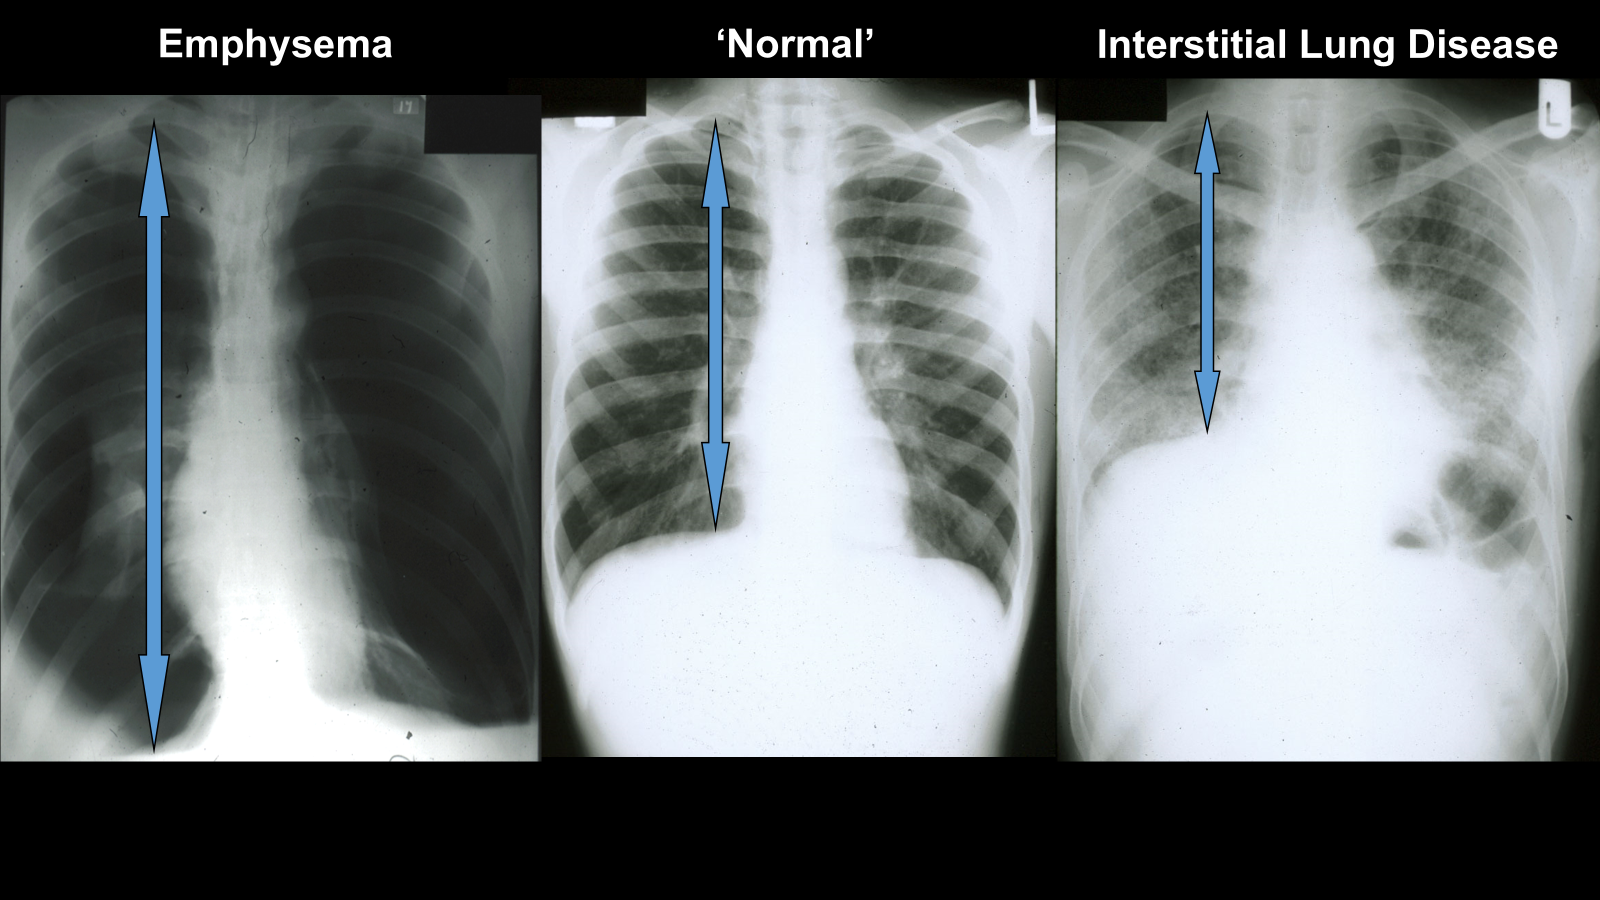

emphysema, increased lung volume as they have to maintain more air in lungs for small airways to breath in and out

interstitial reduced lung volume as less space for air?